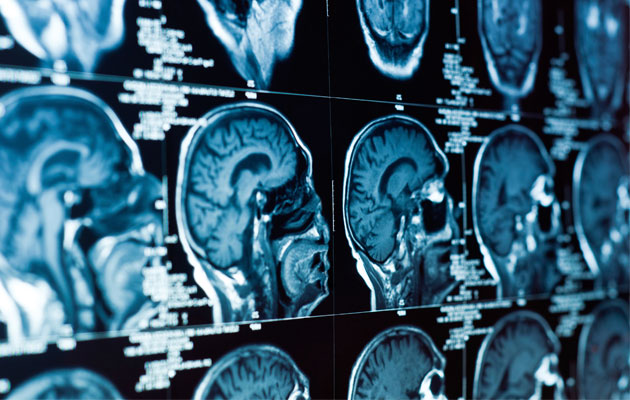

Η Νευρο-ογκολογία έχει ως αντικείμενο τη διάγνωση και τη θεραπεία των όγκων (νεοπλασίες) του Κεντρικού Νευρικού Συστήματος (ΚΝΣ), δηλ. του εγκεφάλου και του νωτιαίου μυελού.

Τα δύο αυτά πολύπλοκα όργανα παρουσιάζουν ανάλογη δυσκολία στη διάγνωση και θεραπεία των όγκων τους.

Το ΚΝΣ προσβάλλεται από περίπου 150 είδη όγκων και οι θεραπευτικές μέθοδοι που τελικά θα επιλεγούν θα πρέπει να προκαλούν μηδενικές βλάβες και ελάχιστες παρενέργειες σ’ αυτό

Εξειδικευμένοι ιατροί αναλύουν διεξοδικά κάθε περιστατικό, διενεργούν εργαστηριακές εξετάσεις για την ταυτοποίηση του όγκου (θέση, μέγεθος, ιστολογικό είδος) και προτείνουν εξατομικευμένη θεραπεία (χειρουργείο, ακτινοθεραπεία, χημειοθεραπεία).